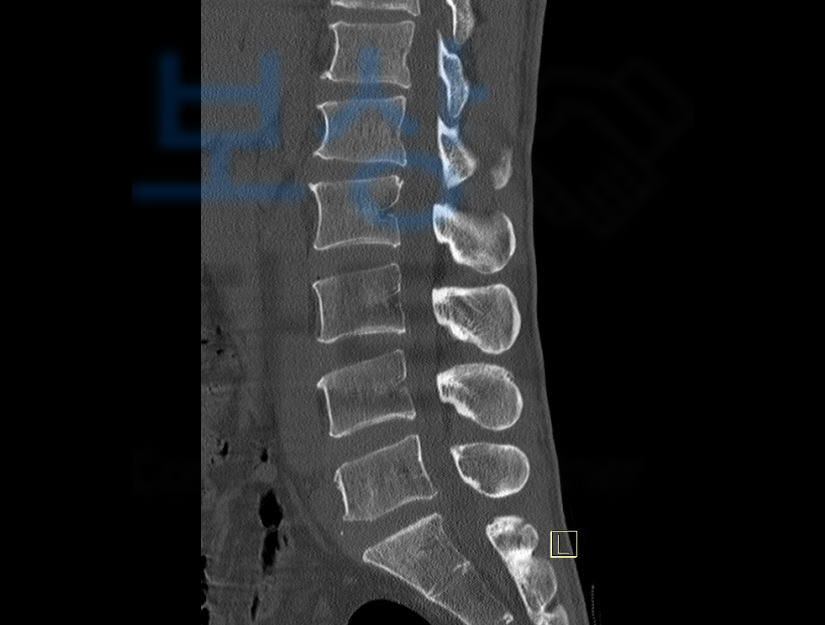

위 진단서 내용처럼 늑골을 침범한 다발골절 S22430 뿐만 아니라

요추 1-3번 골절 S32020, 30, 40

의 진단을 받으셨죠. 위 진단으로 5주간의 요양을 요했지만 척추의 골절은 시간이 경과하면 할수록 몸의 하중에 의해 점점 찌그러지는 형태로 골절이 진행됩니다.

지급받을 수 있었습니다! 게다가 척추, 흉추, 요추 의 골절이시면 더더욱 후유증, 장해 보상 알아 보셔야 합니다.